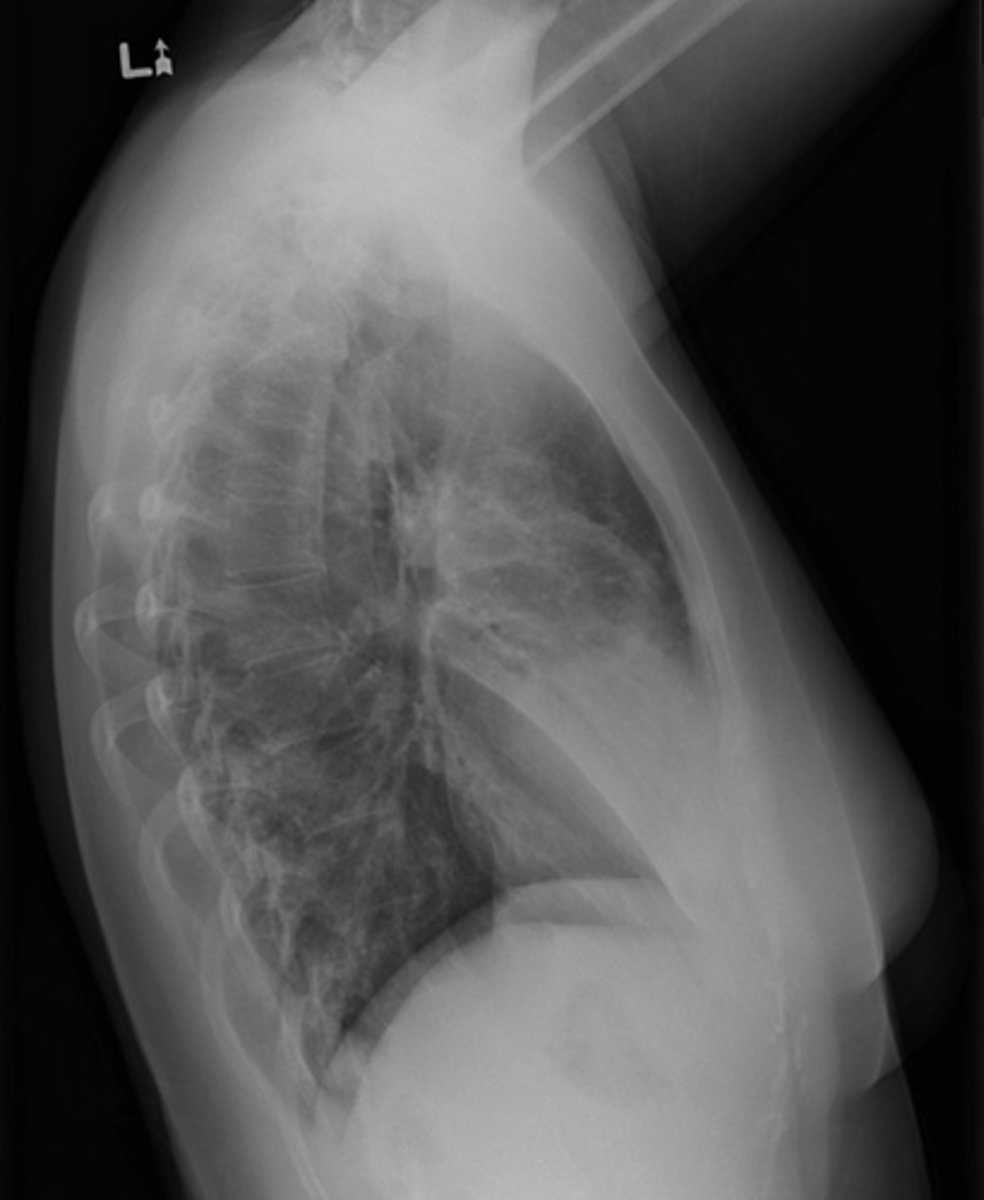

List the 5x components of (S) soft tissues when interpreting plain film radiographs

1. Muscles - atrophy - swelling (ex: swelling around the knee joint as seen in this image)

2. Fat pads and fat lines

3. Joint capsules - effusion

4. Periosteum

5. Miscellaneous

What is a "sail sign"? What is it caused by?

Elevation of a fat pad (ex: when the elbow is injured, it fills up with fluid that pushes the fat pad and lifts it away from the bone itself)

What indicates effusion of a joint capsule on a plain film radiograph?

Radiolucent joint recess due to joint swelling (i.e., effusion) that pushes the proximal superior recess out

List the sub-components of (S) soft tissues: periosteum (sheath outside of cortical bone that sits on top of it)

- Solid

- Laminated

- Sunburst

- Codman's triangle

List the sub-components of (S) soft tissues: miscellaneous

- Foreign body

- Calcifications